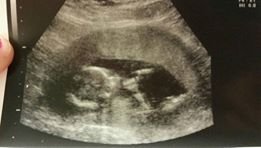

"I recommend this product it def works . I had my first ultra sound Monday . I'm currently 10weeks . Thanks conceive plus!" M.M.R, Facebook, August 12, 2016